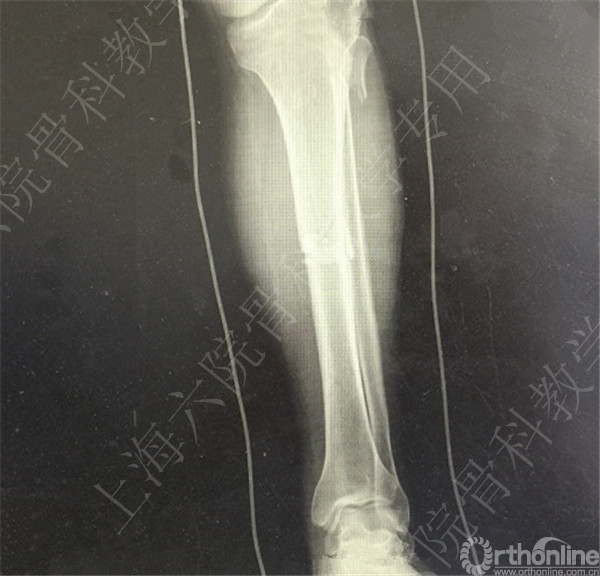

患者车祸伤至左胫腓骨开发性骨折,急诊予清除缝合+外固定术。

待软组织条件好转后,择期行右胫腓骨外固定拆除术+切开复位内固定术。

术后X线摄片示:骨折对位对线欠佳,稍成角。

患者复查,X线摄片示:骨折对位对线差,左胫骨立线欠佳,成角。